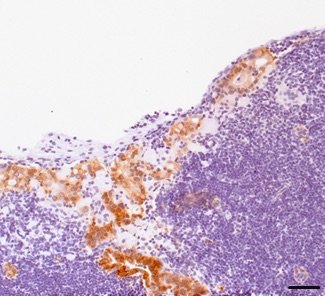

Bei Gesunden arbeiten die Gene Gen Tp53, als auch das Gen Mir34a zusammen. Sie unterdrücken die Signalwege der Krebszellen. Dadurch verhindern sie, dass Krebszellen überleben und in gesundes Gewebe eindringen. Bei einer Erkrankung hemmt das Gen MikroRN miR-34a den IL-6 Rezeptor IL-6R. Der Rezeptor reagiert auf den Botenstoff Interleukin 6 (IL-6), der von der Tumorumgebung produziert wird. Interleukine regulieren die Entzündungsreaktion des Organismus. Dadurch wird die sogenannte epithelial-mesenchymale Transition (EMT) ausgelöst. Dabei handelt es sich um einen zellulären Prozess. EMT fungiert bei einer Dickdarm-Krebserkrankung als Vermittler der Mesastasierung. Gleichzeitig wird das Protein PAI-1 aktiviert. Es sorgt ebenfalls für das Fortschreiten des Primärtumors.

Werden der Il-6R- und der PAI-1-Signalweg therapeutisch inaktivert, verhindert das die Bildung von Metastasen. Dies wurde im Mausmodell nachgewiesen. Laut Forscher spielen gerade diese Signalwege eine große Rolle. Denn sie bieten interessante Ansatzpunkte für die Therapie bei Dickdarmkrebs. Die Wissenschaftler empfehlen deshalb, dies in weiteren Studien zu verfolgen. Für die Forschungsergebnisse wurden 628 Dickdarm-Krebs-Fälle in Online-Datenbänken ausgewertet. Zudem untersuchten die Forscher Proben von 61 Patienten. Die Ergebnisse des präklinischen Mausmodells sind der Analyse zufolge auf den Menschen übertragbar.